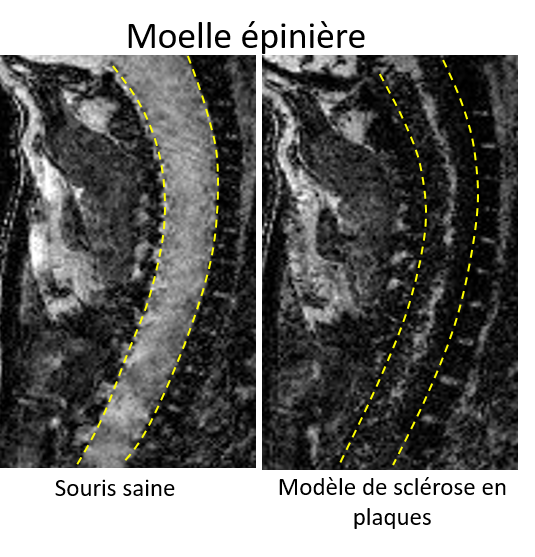

Mercredi 31 mai, se tiendra la Journée mondiale de la sclérose en plaque (SEP), l’occasion pour les associations d’appeler à la mobilisation pour cette maladie neurodégénérative qui touche 100 000 personnes en France et constitue la 1ère cause de handicap non traumatique chez l’adulte jeune. Malgré une évolution en forte progression ces 10 dernières années (4000 nouveaux diagnostics annuels), la maladie reste peu connue, entrainant une errance diagnostic, qui est de 5 ans aujourd’hui. Les associations, et en particulier l’Association française des sclérosés en plaques (Afsep) réclament donc l’obtention du statut de grande cause nationale 2018 et le développement de campagnes d’information et de communication sur ce sujet auprès du grand public. A l’heure actuelle, l’imagerie IRM est largement utilisée pour le diagnostic et le suivi des patients atteints de SEP. Mais des chercheurs français (équipe « SpPrIng » dirigée par Fabian Docagne au sein de l’unité Inserm U1237 de Caen) ont voulu aller plus loin et se sont demandés si cet examen pourrait permettre de prédire l’apparition des poussées. Pour cela, ils ont développé une méthode d’IRM qui permet de suivre dans l’espace et dans le temps l’évolution de la maladie. Elle est basée sur le fait que la sclérose en plaques est due, au moins en partie, au passage de cellules inflammatoires (lymphocytes notamment) dans le cerveau et la moelle épinière à travers la paroi des vaisseaux. Pour pouvoir traverser, les cellules se fixent à des molécules d’adhésion présentes à la surface de vaisseaux sanguins. Les chercheurs ont donc eu l’idée de suivre l’évolution de billes de fer détectables par IRM se fixant sur ces molécules d’adhésion. Ils ont testé cet outil sur des souris présentant un modèle de sclérose en plaques. Dans leur étude, publiée dans la revue Pnas, ils ont montré que l’IRM révèle le passage des cellules inflammatoires et permet ainsi de prédire la survenue d’une poussée chez les souris asymptomatiques et les rémissions chez des souris malades. Les billes de fer sont visualisées en noir, dans la moelle épinière, révélant ainsi une inflammation. "Cette technique pourrait à l’avenir être adaptée chez l’homme pour améliorer le pronostic et le suivi de la maladie chez les patients atteints de sclérose en plaques", conclut l’Inserm.